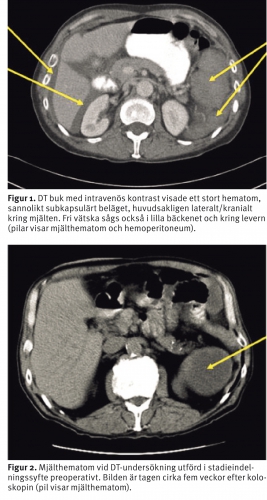

Det första fallet rör en 60-årig kvinna som tidigare opererats för rektalcancer och som genomgår koloskopikontroll för metakron kolorektalcancer vart femte år. Patienten inkom akut tre dagar efter utförd koloskopi med kraftig buksmärta som utstrålade till vänster arm och axill samt vänster arcus costalis. Hon hade varit avsvimmad i hemmet, Hb var 87 g/l. DT buk med intravenös kontrast visade ett mjälthematom och tecken på blod i buken (Figur 1). Patienten behandlades konservativt med blodtransfusion (sammanlagt sex enheter) och övervakades initialt på IVA. Den totala vårdtiden var sju dygn.

Det andra fallet rör en 65-årig man som opererades akut för kolonileus på ett annat sjukhus. Patienten erhöll en transversostomi på grund av strikturerande sigmoideumcancer, och man planerade för definitiv operation i ett senare skede. Han utreddes med koloskopi via stomin inför den slutgiltiga operationen. Preoperativ DT buk med intravenös kontrast, som utfördes en månad efter koloskopin, visade ett mjälthematom (Figur 2). Enligt koloskopiberättelsen var skopin besvärlig i vänster kolon, och på direkt förfrågan senare bejakade patienten förekomst av ihållande vänstersidig buksmärta, som så småningom avtog efter koloskopin.

Patienter med misstänkt mjältskada bör omgående genomgå DT buk med intravenös kontrast för att verifiera diagnosen och differentiera mellan avgränsad laceration/subkapsulärt hematom och hemoperitoneum. Den intravenösa kontrasten visar skadans omfattning och eventuell pågående blödning.